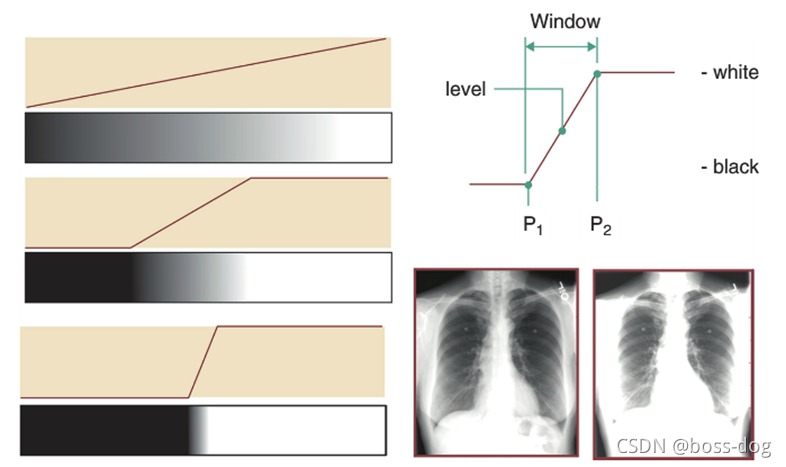

Display contrast(显示器地对比度)

医学图片中希望把最黑的、最亮的、中间的能够完美地显示出来。

上图中如何将灰度转换为显示器上的实际密度:

窗口宽度(Window width,W)

window level(L)

饱和至黑色:L - W/2

饱和至白色:L + W/2

1.检测器信号范围是0-4000计数/像素。

2.PC显示器相对亮度0-2000。

3.图像具有有用区域的信号范围为500-3000计数/像素。

像CT的话,窗口很宽,从负一千到正一千,如果全部显示出来的话,人眼不一定能够把那些细节检测出来看出来,所以针对CT,可以调整图像。